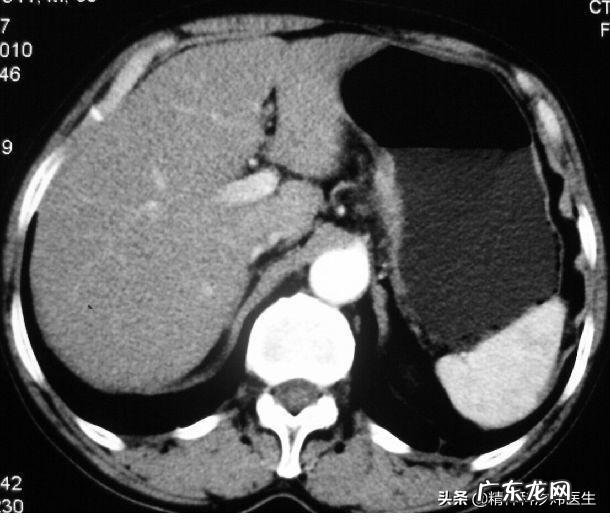

根据胃镜检查 , 将胃癌分期分为早期胃癌和进展期胃癌

早期胃癌:指的是局限于黏膜或粘膜下层的癌 。胃镜下可见小的息肉样隆起(也就是我们说的癌灶) , 其中 , 癌灶直径小于1㎝的称之为小胃癌;小于0.5㎝的称之为微小胃癌 。

进展期胃癌又称中晚期胃癌 , 指的是癌组织浸润超过黏膜下层或浸润胃壁全层的胃癌 , 可以想象的是 , 浸润越深 , 预后越差 。